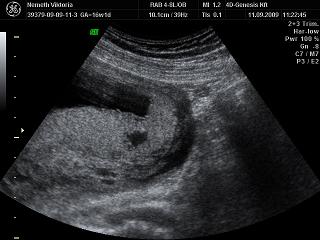

Tök sokára jutottam be, mert ugye nem volt időpontom. Meg ultrahangozott a doki, hát érdekes volt. Először nem mondott semmit, csak a végén közölte, hogy ok, most menjek el sétálni, negyed órára és majd visszahívnak, mert nem jól fekszik a baba

én még ilyen nehézkes nyaki redő mérést nem pipáltam... ok lementem gyalog a lépcsőn, ittam egy kávét, majd fel gyalog a negyedikig. Na ez meg is tette hatását- mikor visszahívtak, elkezdte mérni, megmérte vagy tízszer (!!!) a nyaki redőt. Nem mondott semmit. De én láttam alul a sarokban, hogy oda volt írva az NT, és hogy folyton ilyeneket mért, hogy 2,1,2,2,2,3....stb. mindig ekörül. Már törölgette a homlokát, összenéztek az asszisztenssel... kezdtem nagyon unni. Mondja egy idő után, hogy hát ő nem érti, de neki meg sem közelíti a 3-at.... mondja max 2.3-at mért idáig. Na mondom, az jobban hangzik, mint a 3.3. Akkor utána elkezdett a gyerek pörögni, kiegyenesedett, akkor is ilyeneket méregetett, majd a lepénytapadásra semmit nem mondott

, és mikor a gyerek kicsit hátrahajtotta a fejét, na akkor mért 2,8-3-at. És utána mondta, hogy ne haragudjak, de akkor ezt írja be, mert ha kicsit hátrahajtja a fejét, akkor vastagabb. De, szerinte nincs az 3 se, mindenesetre menjek el genetikai tanácsadásra....

Szoval tudjátok mit nem értek??? Nem az a normál állapot, ha nincs a feje hátrahajtva? Mikor pl. magasságot mérnek, akkor sem érvényes, ha hátrahajtom a fejemet,nem? Sőt ha a fejemet hátrahajtom, az én nyakam is vastagabb lesz, és megrövidül nem? Szerintetek másnak a nyaki redőjét is úgy mérik, hogy megvárják, míg hátrahajtja a fejét?!?!? Nem értem az egészet, komolyan... mindegy, a lényeg, hogy még így is kevesebbet mértek. szoval holnap megyek 11:30-ra a Bolgárkerékre a 4d uh-ra és a kombinált tesztre utána.